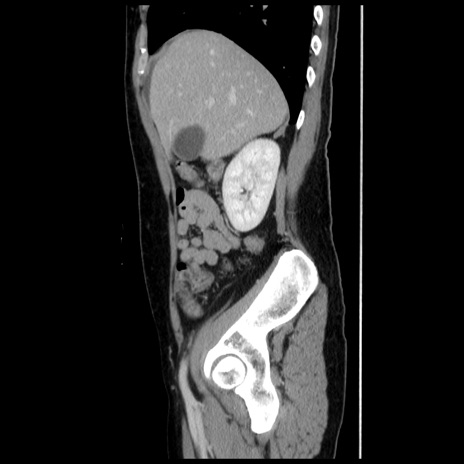

症例10(矢状断像)

【症例】 50歳代女性

【主訴】 腹痛

【現病歴】前日生レバーを食べた。今朝に排便あり。 昼前に突然発症の腹痛を生じ、当院救急外来を受診した。

【既往歴】 子宮筋腫にてで子宮全摘後

【身体所見】 意識清明、腹部:平坦、軟、下腹部やや左を中心に圧痛・反跳痛あり、筋性防御あり

【データ】WBC 7800、CRP 0.07